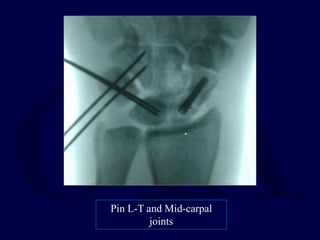

Pin Carpus: S-L,

carpal joints

Pin L-T and Mid-carpal

joints